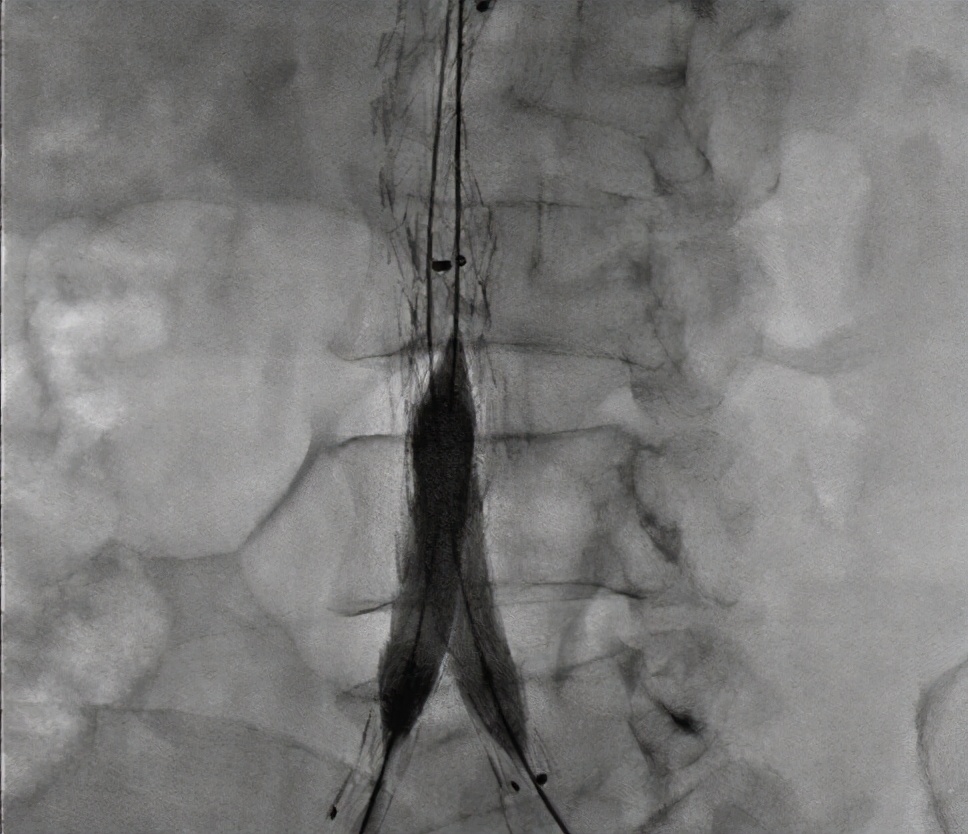

④主动脉造影

典型的小叶囊性动脉瘤,通常为多发或连续型。主动脉壁有无动脉硬化。因为覆盖了血栓或周围组织,血栓可能是不规则的,当血栓充满肿瘤腔时不能形成。